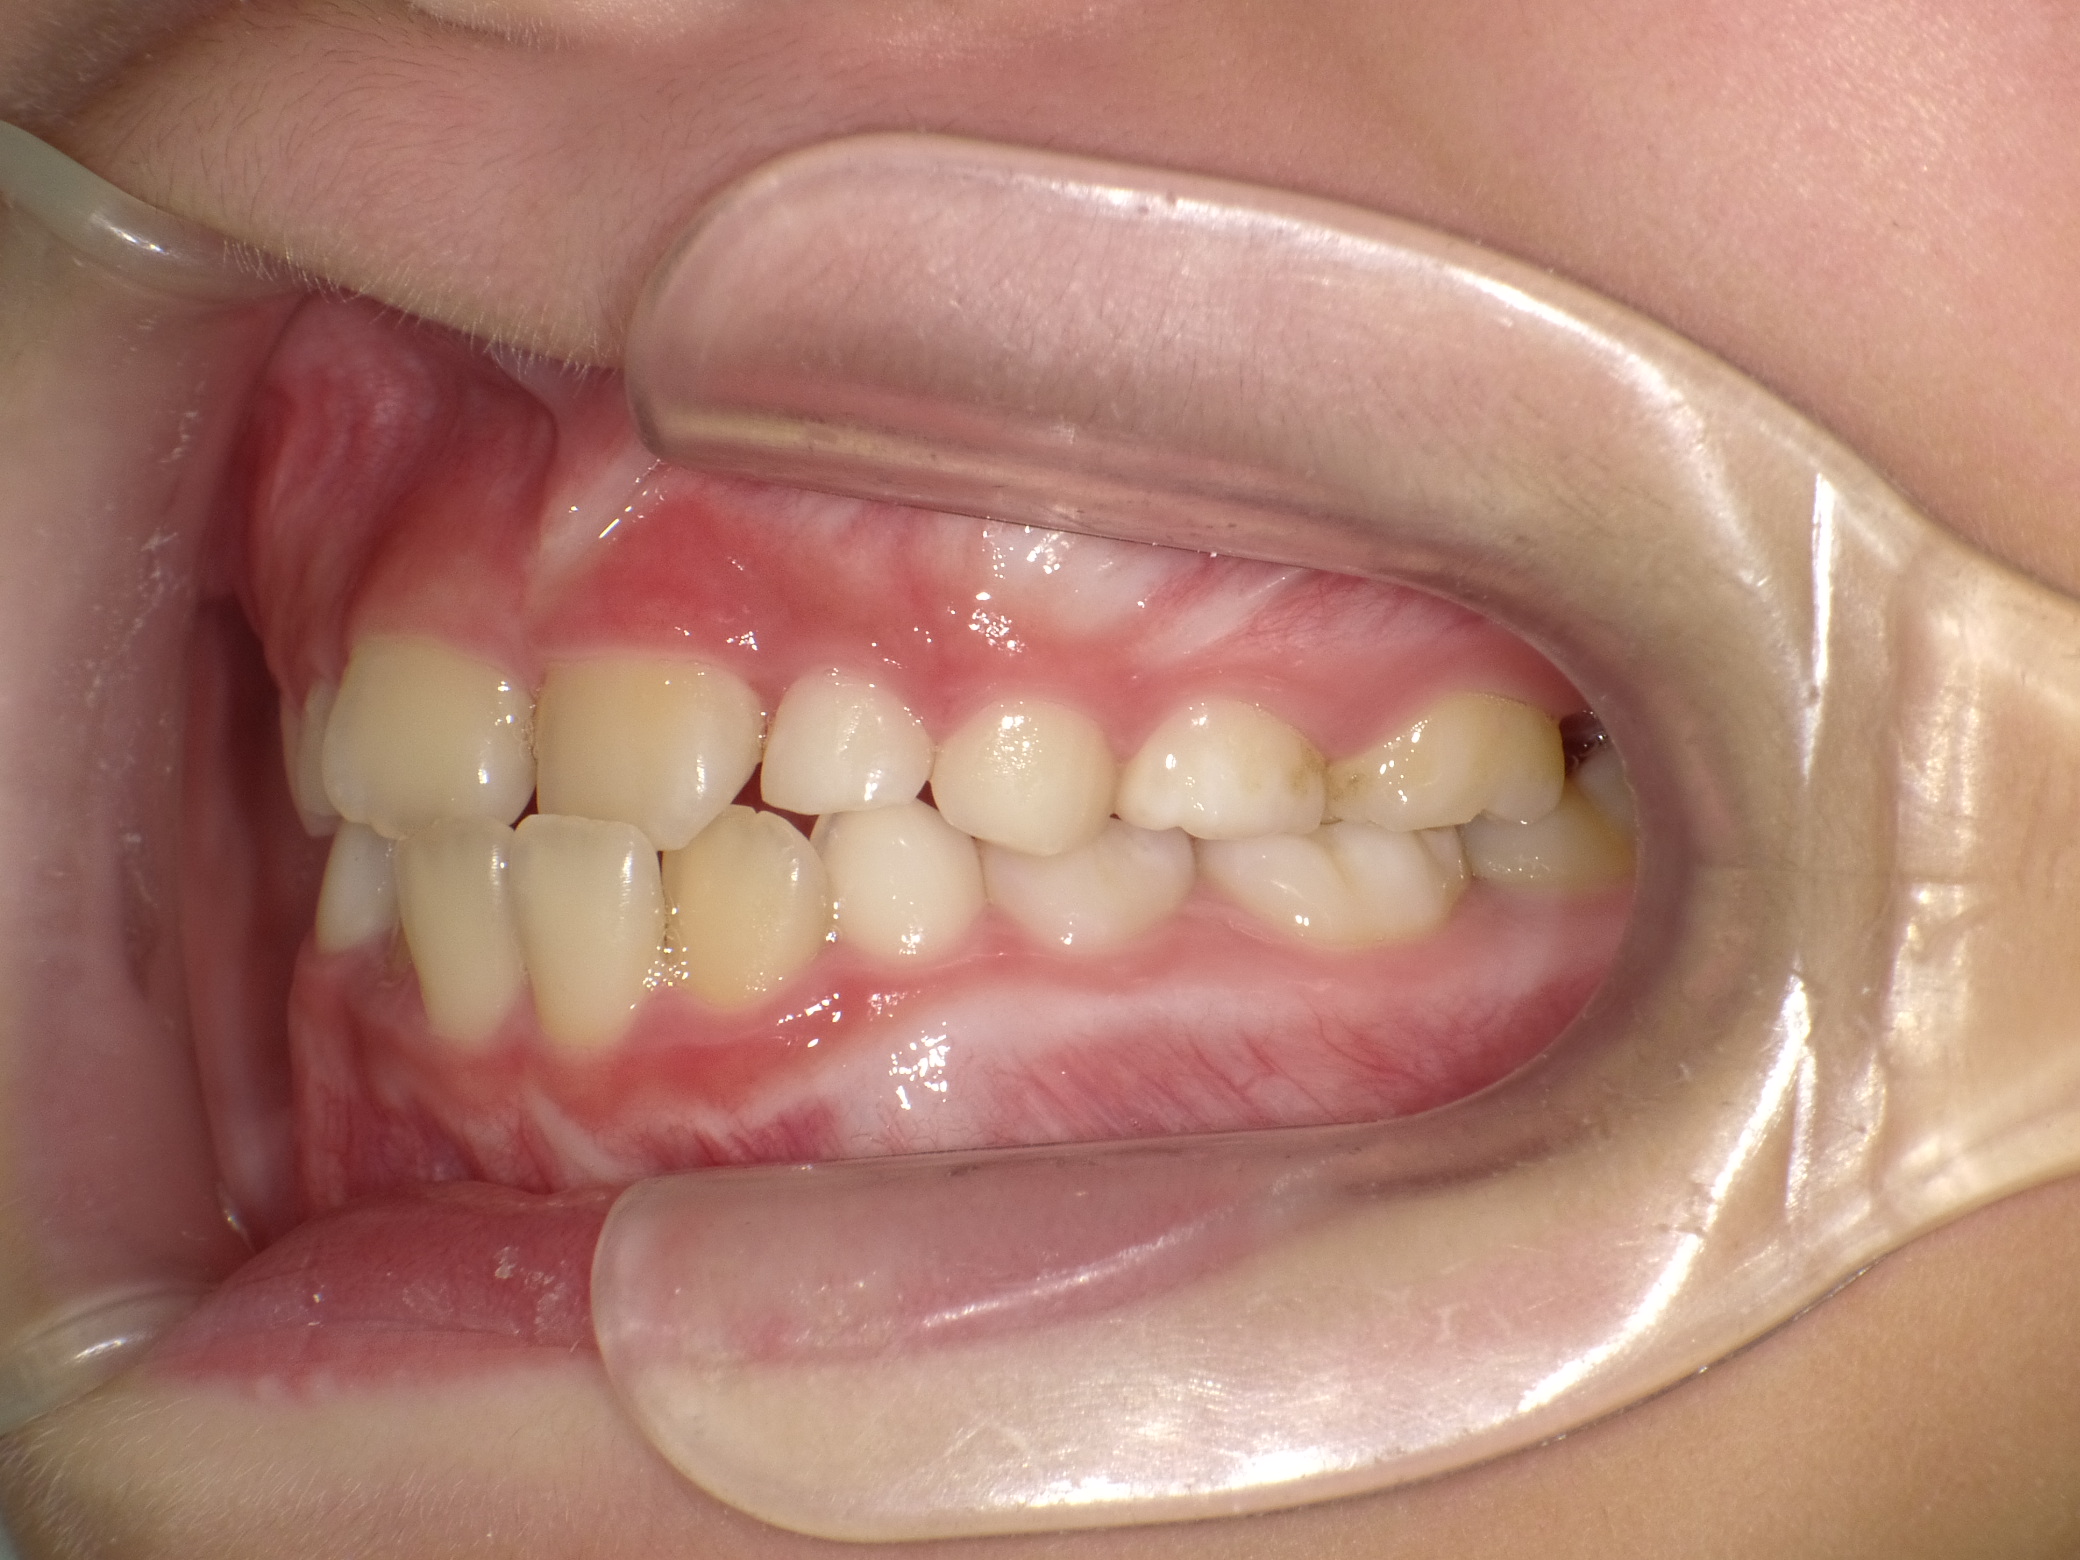

【小学生】マイオブレース矯正 反対咬合を改善

小学生で開始

マイオブレース

受け口

非抜歯

1期治療のみで改善

Before

After

治療期間

1.6年

治療開始

8歳

種類

マイオブレース矯正

使用装置

機能矯正装置

コメント

治療にしっかり取り組んでくれたのでスムーズに治りました。

治療後3年経過した今でも 装置もいれずに 後戻りもしていません。